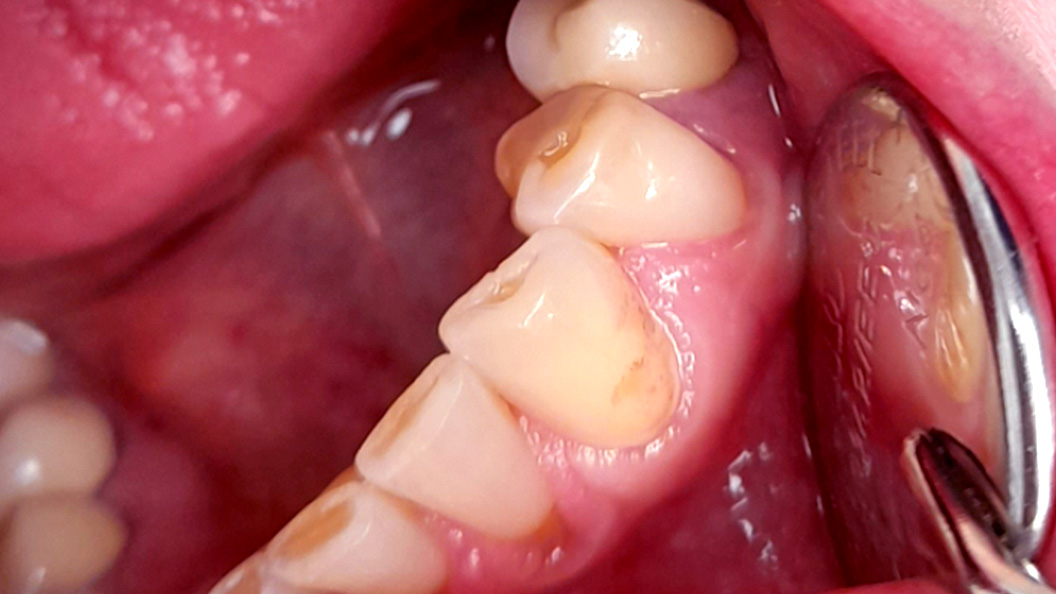

До и после лечения

В стоматологию обратилась пациентка с жалобами на быстро проходящую боль от холодного в районе клыка нижней челюсти. Врач провёл осмотр, а также реакцию зуба на холодный воздух и зондирование. В результате выявлена кариозная полость. Поставлен диагноз — средний кариес зуба 3.3 (вестибулярно). Проведено лечение с использованием композита светового отверждения Эстелайт.

В ходе лечения врач провёл следующие манипуляции:

- инфильтрационная анестезия;

- ретракция десны нитью;

- механическая и медикаментозная обработка кариозной полости;

- наложение изолирующей прокладки;

- постановка пломбы из материала Эстелайт.